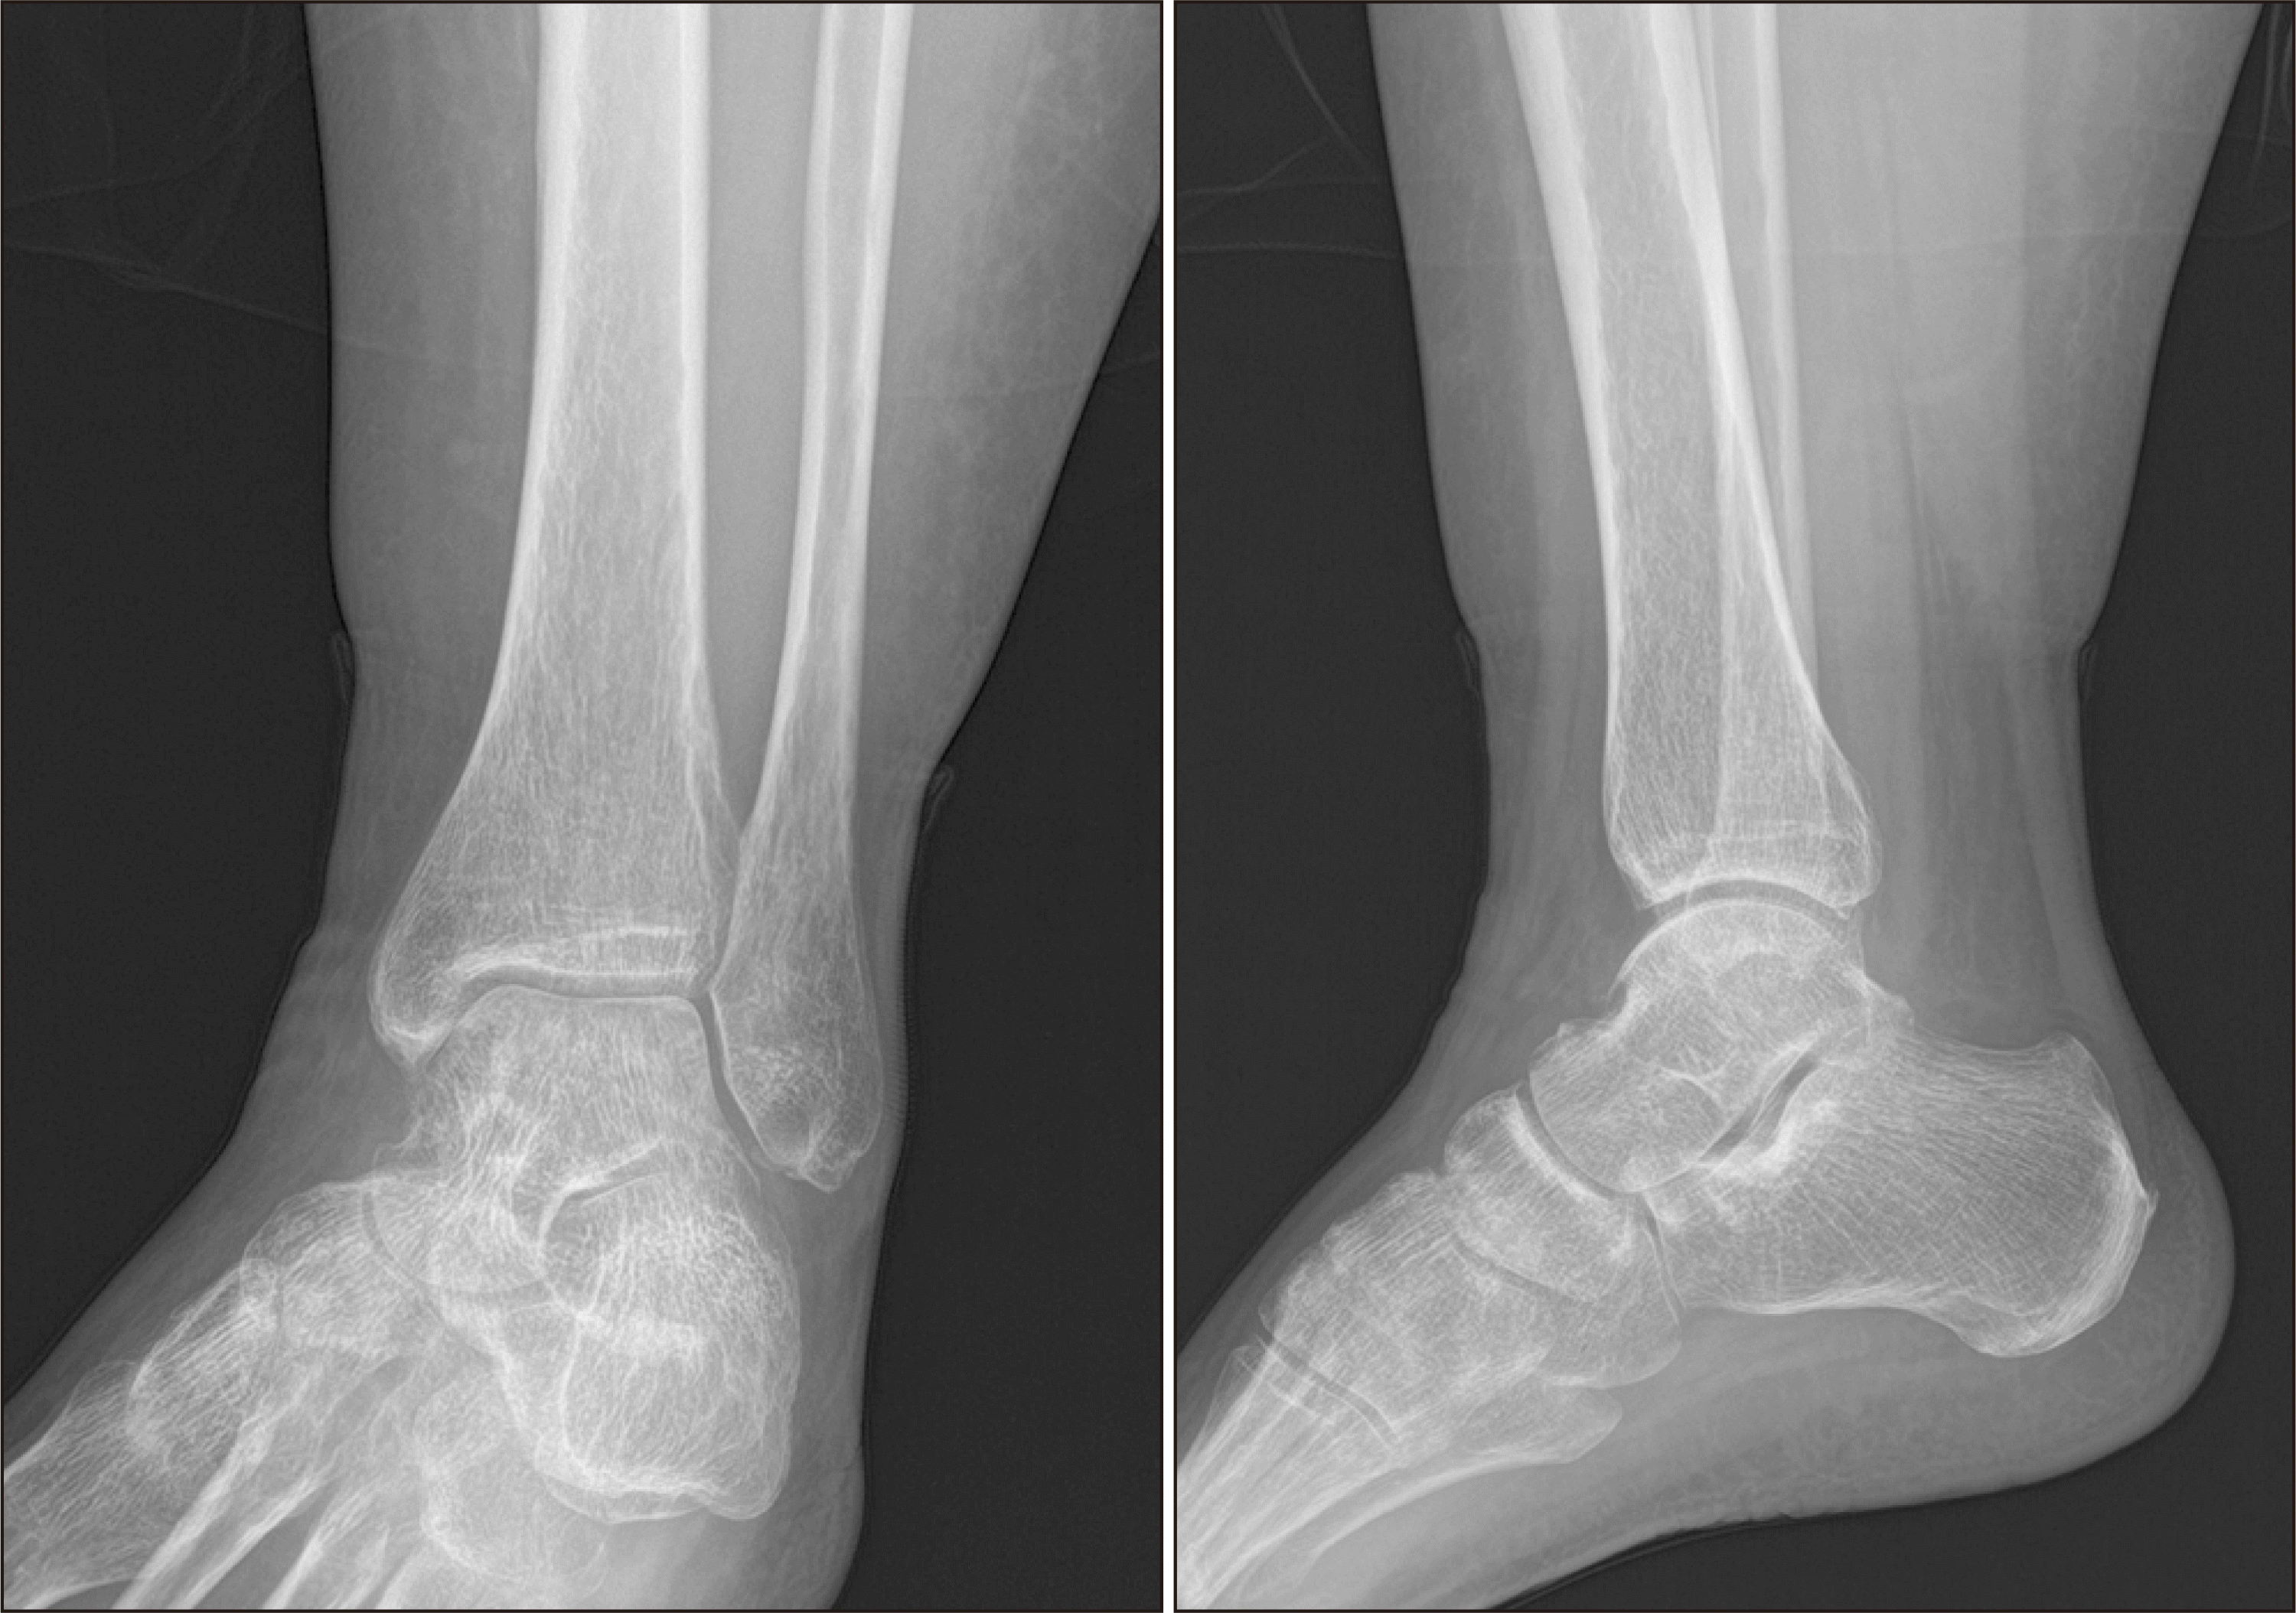

Figure 1

Simple radiographs of the left ankle show an avulsion fracture of the lateral malleolus (arrow).